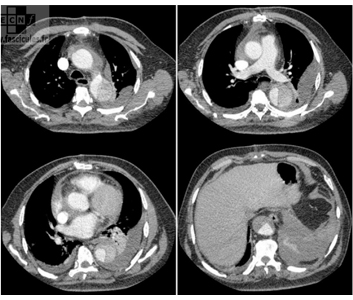

Le scanner utilise les rayons X et à l’intérieur du statif, il existe de part et d’autre de la table d’examen un tube à rayon X et un récepteur (barrette) qui tournent autour de la partie du corps à examiner; Pour chaque image, vous entendez le bruit de cette rotation.

Le mince pinceau de rayon X permet d’effectuer des coupes avec une dose très faible, qui apparaissent sur un écran de télévision après avoir été reconstruites dans un ordinateur.